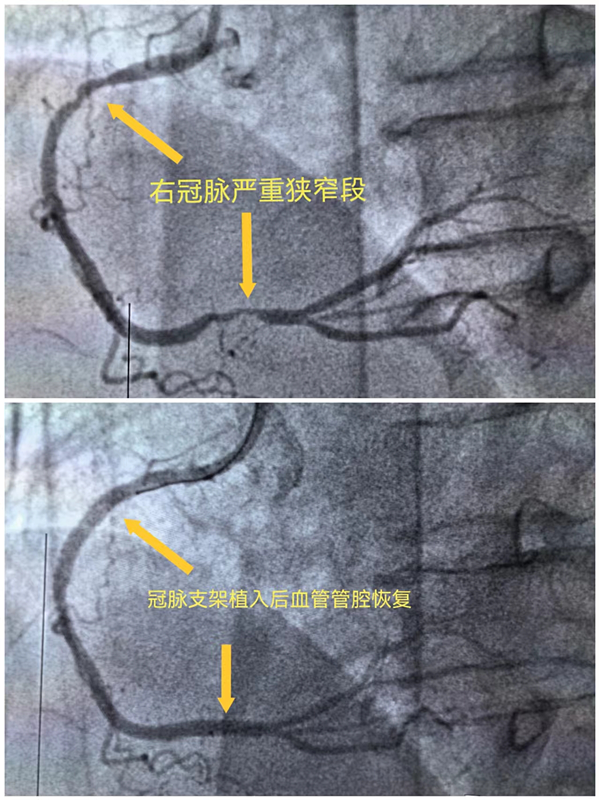

是心脏更重要还是大脑更重要?答案是都重要!广西科技大学第一附属医院胸痛中心、卒中中心联合启动导管室,立即为患者行一站式心脑血管造影,造影显示患者冠脉血管有狭窄但已再通,考虑是用药后血管再通,而脑动脉造影显示患者右椎动脉狭窄达99%!根据泛血管管理中心多学科会诊机制,经心血管内科、神经内科、导管室联合会诊商讨决定,考虑冠状动脉用药后血管再通,患者目前右椎动脉病变更严重,优先处理椎动脉病变,于是在术中经桡动脉入路于右椎动脉开口处为患者植入支架一枚,解除血管狭窄,全程只有右侧桡动脉一个穿刺点。术后患者胸痛已缓解,恢复言语后马上转到心血管内科接力救治,并于5天后经鼻烟壶区远端桡动脉穿刺入路完成右冠脉严重狭窄段支架植入术。这是我院首例经桡动脉入路椎动脉支架植入术,患者术后恢复更快、体验更佳。